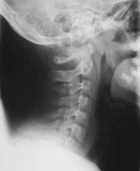

C.F. - 15 year old female presents with a six month hx of neck pain.

Zoom image: Radiological image Radiological image.